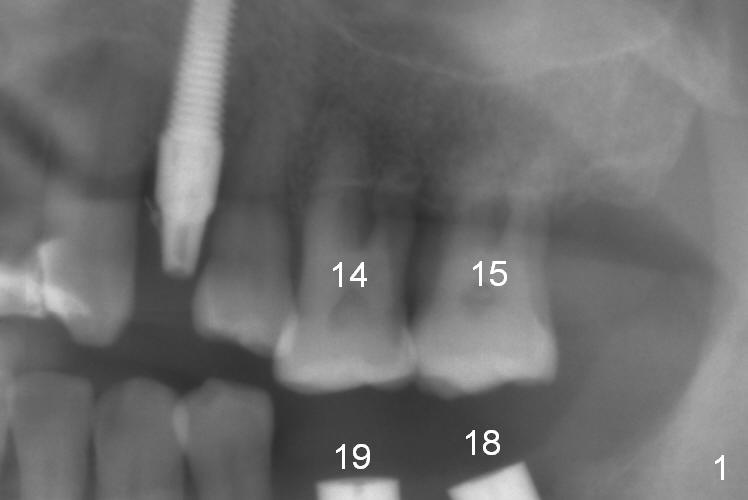

The teeth #14 and 15 of a 42-year-old man are supraerupted when implants are placed at #18 and 19 (Fig.1). Intrusion takes 6 months with 3 mini-implants. Fig.2 is taken 2 years after treatment.